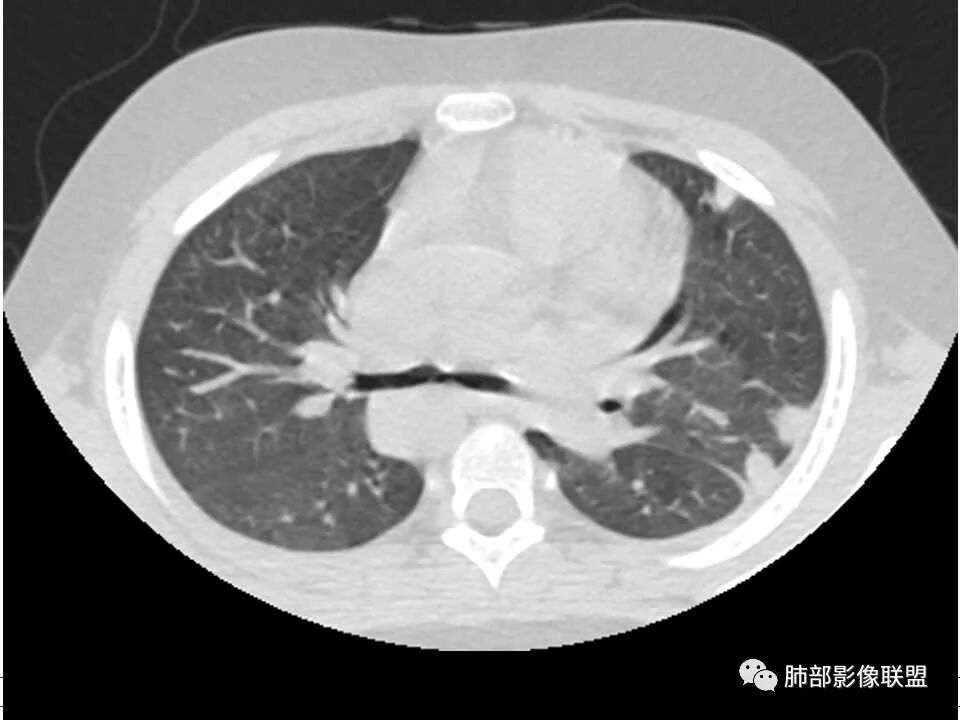

晨读,儿童,起病急,病程短,有下肢疼痛伴肿胀病史,发热,白细胞升高,结合下肢辅查,考虑骨髓炎,胸部ct:双肺多发空洞,结节,外带下叶为主,空洞内外光滑,无丝状物,有血管滋养征,综合病史及影像考虑脓毒性肺栓塞,金葡可能性大,建议痰培养,血培养,必要时ngs。

双肺多发空洞、结节及胸膜下楔形密度增高影,结合临床考虑:1.金葡菌肺感染。2脓毒性肺栓塞。

双肺多发结节,空洞,与胸膜相连,血道来源,空洞内壁光滑,结节周围模糊,考虑金葡菌感染。

有脓毒性肺栓塞了,有空洞,有结节,有血管滋养征,考虑血源性金葡菌感染

胸部ct:双肺多发空洞,结节,外带下叶为主,空洞内外光滑,有血管滋养征,综合病史及影像考虑脓毒性肺栓塞,结合病史,金葡可能性大。

小儿,急性起病,下肢疼痛,mr提示骨髓水肿,临床化验炎性指标高,考虑金葡菌骨髓炎,双肺多发结节,以血管支气管束及胸膜下分布为主,部分结节近端与血管相连,部分结节可见空腔,内壁光整,部分囊腔有张力,考虑骨髓炎并肺内血播感染,金葡?

2.双肺多发片影,随机分布,多空洞或囊腔,胸膜下多楔形影,气道未见受累等等符合脓毒血症影像学表现,尤其是金葡。

1. 多发胸膜下外周结节、< 3 cm 的楔形影和滋养血管征 CT 表现;

4.经恰当的抗生素治疗,肺部浸润影吸收。滋养血管征为一支血管影连接肺部周边病灶,在 2/3 以上患者出现,可作为高度提示 SPE 的征象。